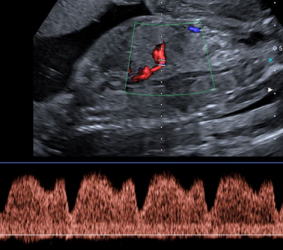

Untersuchung des fetalen Herzens (fetale Echokardiographie)

Bei einer solchen Untersuchung wird das Herz des Feten mittels hochauflösender Ultraschallgeräte im Detail untersucht. Ferner können mit Hilfe der Doppler-Sonographie die Blutflüsse im Herzen und in den angrenzenden Blutgefäßen dargestellt werden.

Relevante Verengungen und Störungen der Herzklappenfunktion können erkannt werden. In der überwiegenden Zahl der Fälle kann so eine kindliche Herzerkrankung ausgeschlossen werden.

Bei einigen wenigen Kindern wird dagegen bereits vorgeburtlich ein Herzfehler oder eine Herzerkrankung erkannt. Eine exakte Diagnose erlaubt eine frühzeitige Beratung mit Kinderkardiologen und Herzchirurgen, um eine optimale Betreuung des Kindes vor und nach Geburt zu gewährleisten. Häufig wird die Entbindung in solchen Fällen in Zentren mit entsprechenden Spezialisten geplant.

Prinzipiell kann man das fetale Herz jenseits der 12.-13. SSW untersuchen. Es können dann etwa 50-60 % der schweren Herzfehler erkannt werden. Allerdings ist zu diesem frühen Zeitpunkt die Zuverlässigkeit der Untersuchung wegen der geringen Größe des fetalen Herzens eingeschränkt, so daß meist zu einer nochmaligen Untersuchung geraten wird. Als günstigsten Untersuchungszeitpunkt wird die 20.-22. SSW empfohlen, in diesem Zeitraum können speziell ausgebildete Untersucher nahezu 80 % aller Herzfehler erkennen. Selbstverständlich kann diese Untersuchung bei Verdacht auf einen fetalen Herzfehler, einer Herzrhythmusstörung oder Nachweis einer anderen Entwicklungsstörung in jedem Schwangerschaftsalter erfolgen.